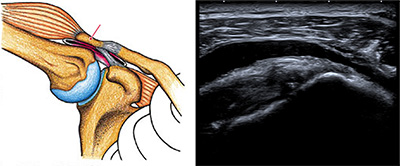

腱板とは肩甲骨と上腕骨を繋いでいる筋肉です。この腱板の機能としては上腕骨を安定化させ、腕を挙げる重要な役割を担っております。

当院では、まず初診時にエコーを用いて断裂の有無を確認します。断裂がある場合はそれが変性(加齢性変化)によるものなのか外傷性(転倒など)によるものかをエコーの所見より明らかにし、断裂サイズ、患者様の活動レベルに合わせてオーダーメイド治療を開始していきます。(エコーで診断が付きにくい場合はMRIを施行します。)約半数は3~6か月で症状が改善します。症状が改善した場合はそのまま保存療法を選択し定期的にレントゲンで変形の程度、エコーを用いて断裂サイズが変わってないかを慎重に診ていきます。

肩関節にとって「腱板」という組織が非常に重要な働きをします。しかし、レントゲンでは腱板の評価を行う事は出来ません。

当院では「腱板」の評価を初診時にエコーを用いて判断します。

更にエコーを用いてピンポイントで炎症が起きている部分に注射をすることで、確実に痛みを取り除き治療を進めていきます。